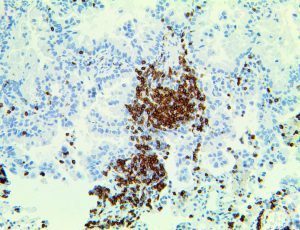

It is the ICU physician who is most likely to witness one of the deadliest manifestations of the abnormal immunological response, the cytokine storm syndrome (CSS). This response is also referred to by some as the cytokine release syndrome (CRS). CSS is characterized by continuous activation and expansion of macrophage and lymphocyte populations, which secrete large amounts of cytokines, causing the cytokine storm. This massive cytokine release is akin to hemophagocytic lymphohistiocytosis (HLH) disease, a syndrome characterized by initial unchecked and persistent activation of cytotoxic T lymphocytes and NK cells.

Clinical and laboratory manifestations of HLH include fever, enlarged liver and/or spleen, neurologic dysfunction, coagulopathy, liver dysfunction, cytopenias (i.e., low levels of erythrocytes, leukocytes, and/or platelets), hypertriglyceridemia, hyperferritinemia, hemophagocytosis, and eventually diminished NK cell activity as the immune system becomes progressively paralyzed. HLH can be familial (primary HLH) or secondary to another disease process (sHLH), such as rheumatic disease, in which it is referred to as macrophage activation syndrome (MAS, characterized by elevated ferritin).